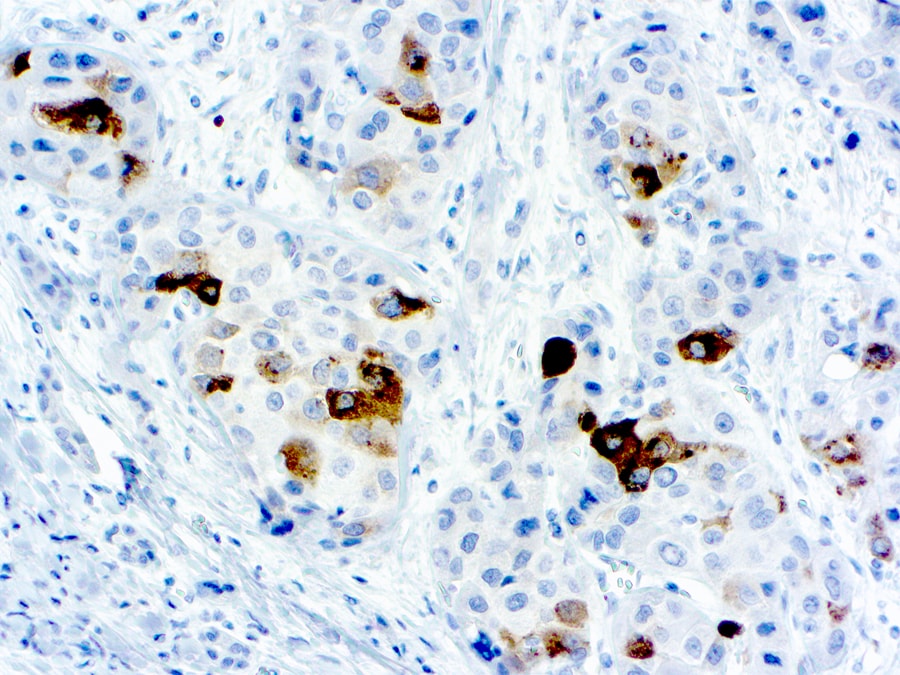

Specificity: This antibody reacts with alpha-1-fetoprotein. A positive staining in the hepatocytes of fetal tissue was observed. This antibody does not react with other cell or tissue types.